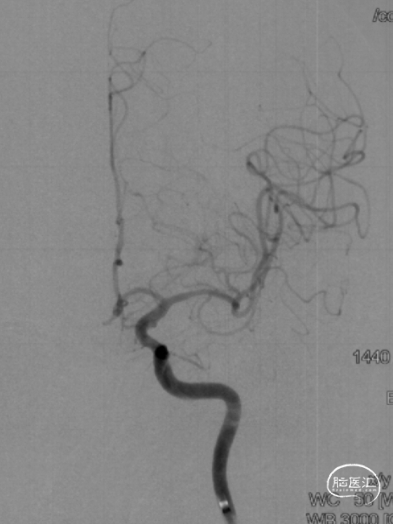

6F Envoy DA导引导管到位,Synchro2微导丝通过病变。

选用1.5-9mm 颅内球囊扩张导管通过病变。

10atm扩张90s。

泄球囊后可见狭窄明显改善。

选用赛诺神畅 3.5-20mm COMETIU™自膨式颅内药物涂层支架系统通过病变并缓慢释放,释放后造影,支架定位准确,完全覆盖病变,成形效果好。

撤出导管导丝后造影,可见靶血管支架贴壁良好,前向血流通畅稳定。

2022-07-27 COMETIU™自膨式颅内药物涂层支架 3.5-20mm (正位)

2022-07-27 COMETIU™自膨式颅内药物涂层支架 3.5-20mm (侧位)